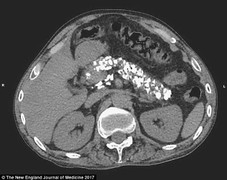

Triệu chứng ung thư tuyến tụy giai đoạn đầu

Ung thư tuyến tụy thường phát hiện khi ở giai đoạn muộn, gây khó cho điều trị, vì vậy việc nắm triệu chứng ung thư tuyến tụy giai đoạn đầu rất quan trọng.